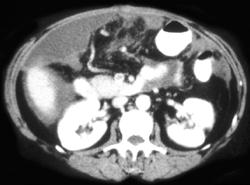

Gastric Adenocarcinoma